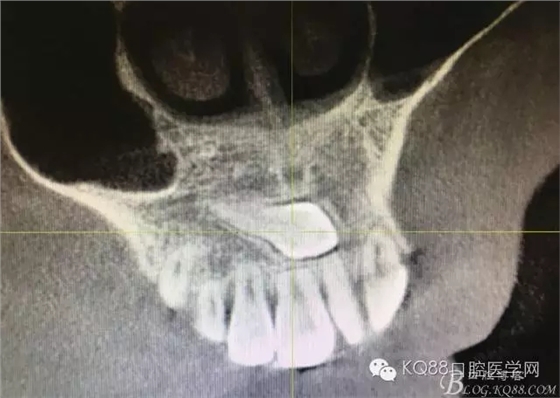

圖4.冠狀面檢查情況 :